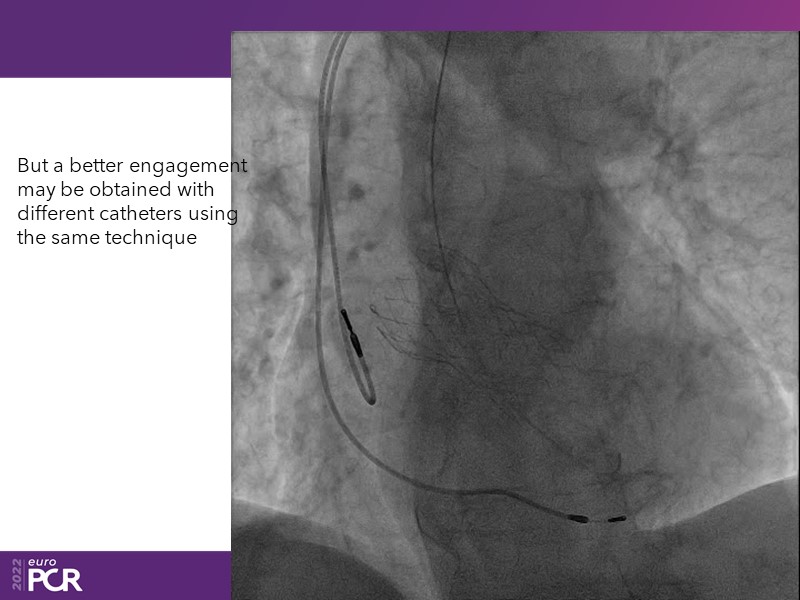

Consult this session to learn how to contribute to streamlined pre- and post-TAVI patient pathways, to discover updates on the optimised TAVI procedure and appreciate the variances in different valve designs and the long-term patient outcomes, as well as to discuss the right time of PCI in TAVI patients (steps on the procedure).

- To discuss the right time of PCI in TAVI patients (steps on the procedure)